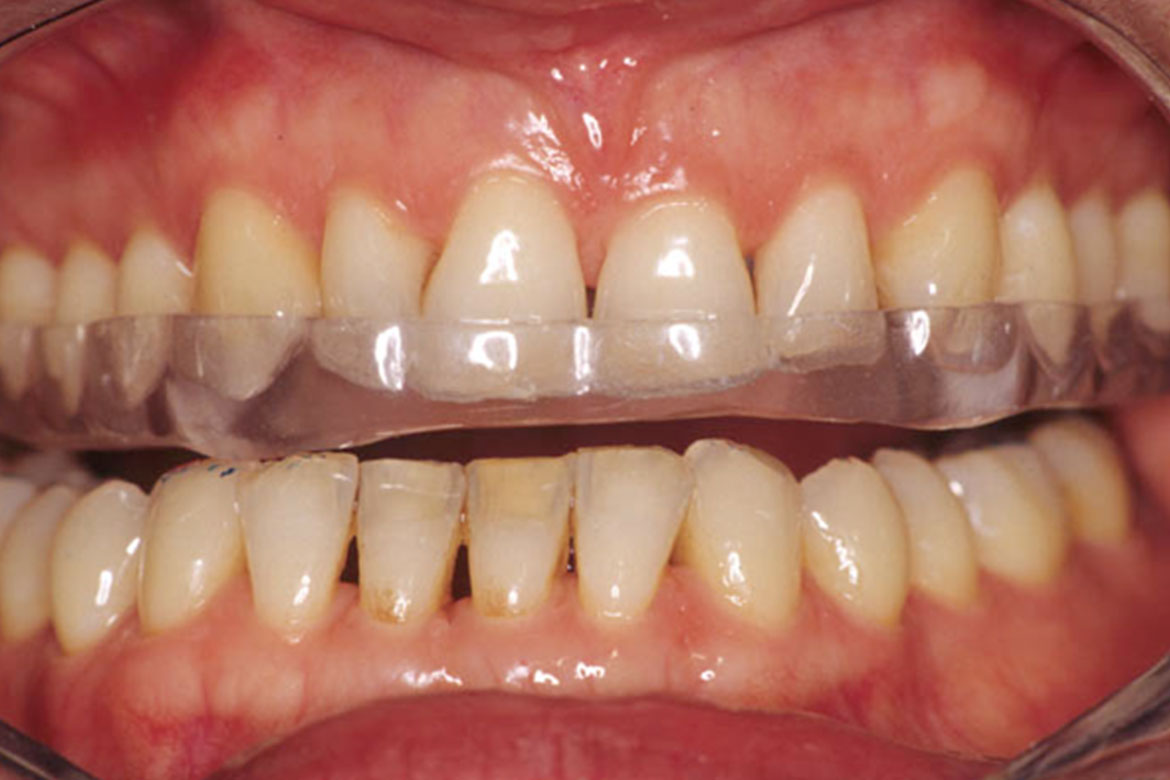

Bruxisme et usure dentaire